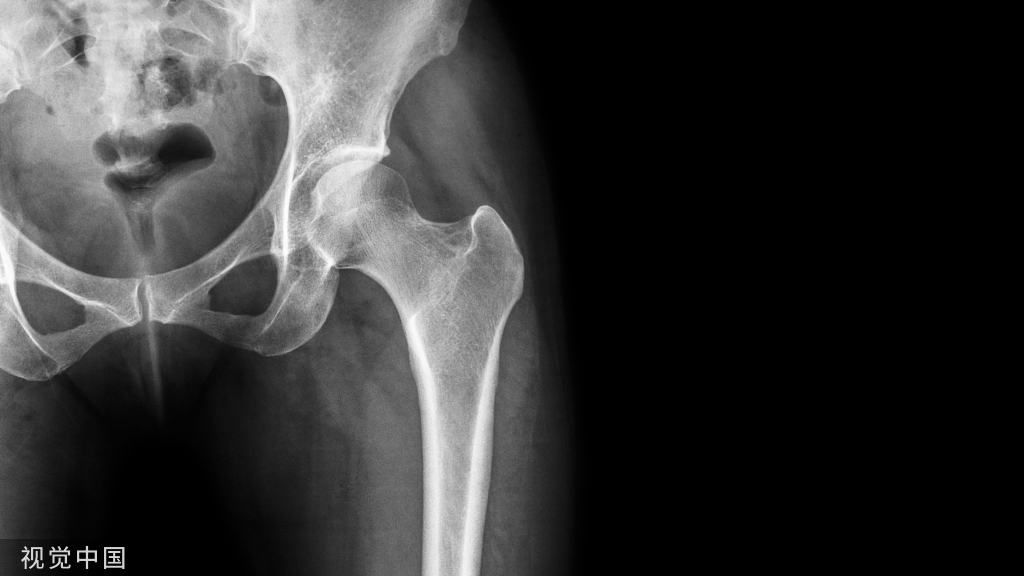

一张标准的胶片,医生最终的着眼点往往只在2-3mm的致病处,只有拍清楚细节部分,医生才能够给出准确的答复,所以分格的片子应该每4-6小格拍一张,不能图省事整张拍摄,那是自己糊弄自己啊,为了您的病情,辛苦一点吧。